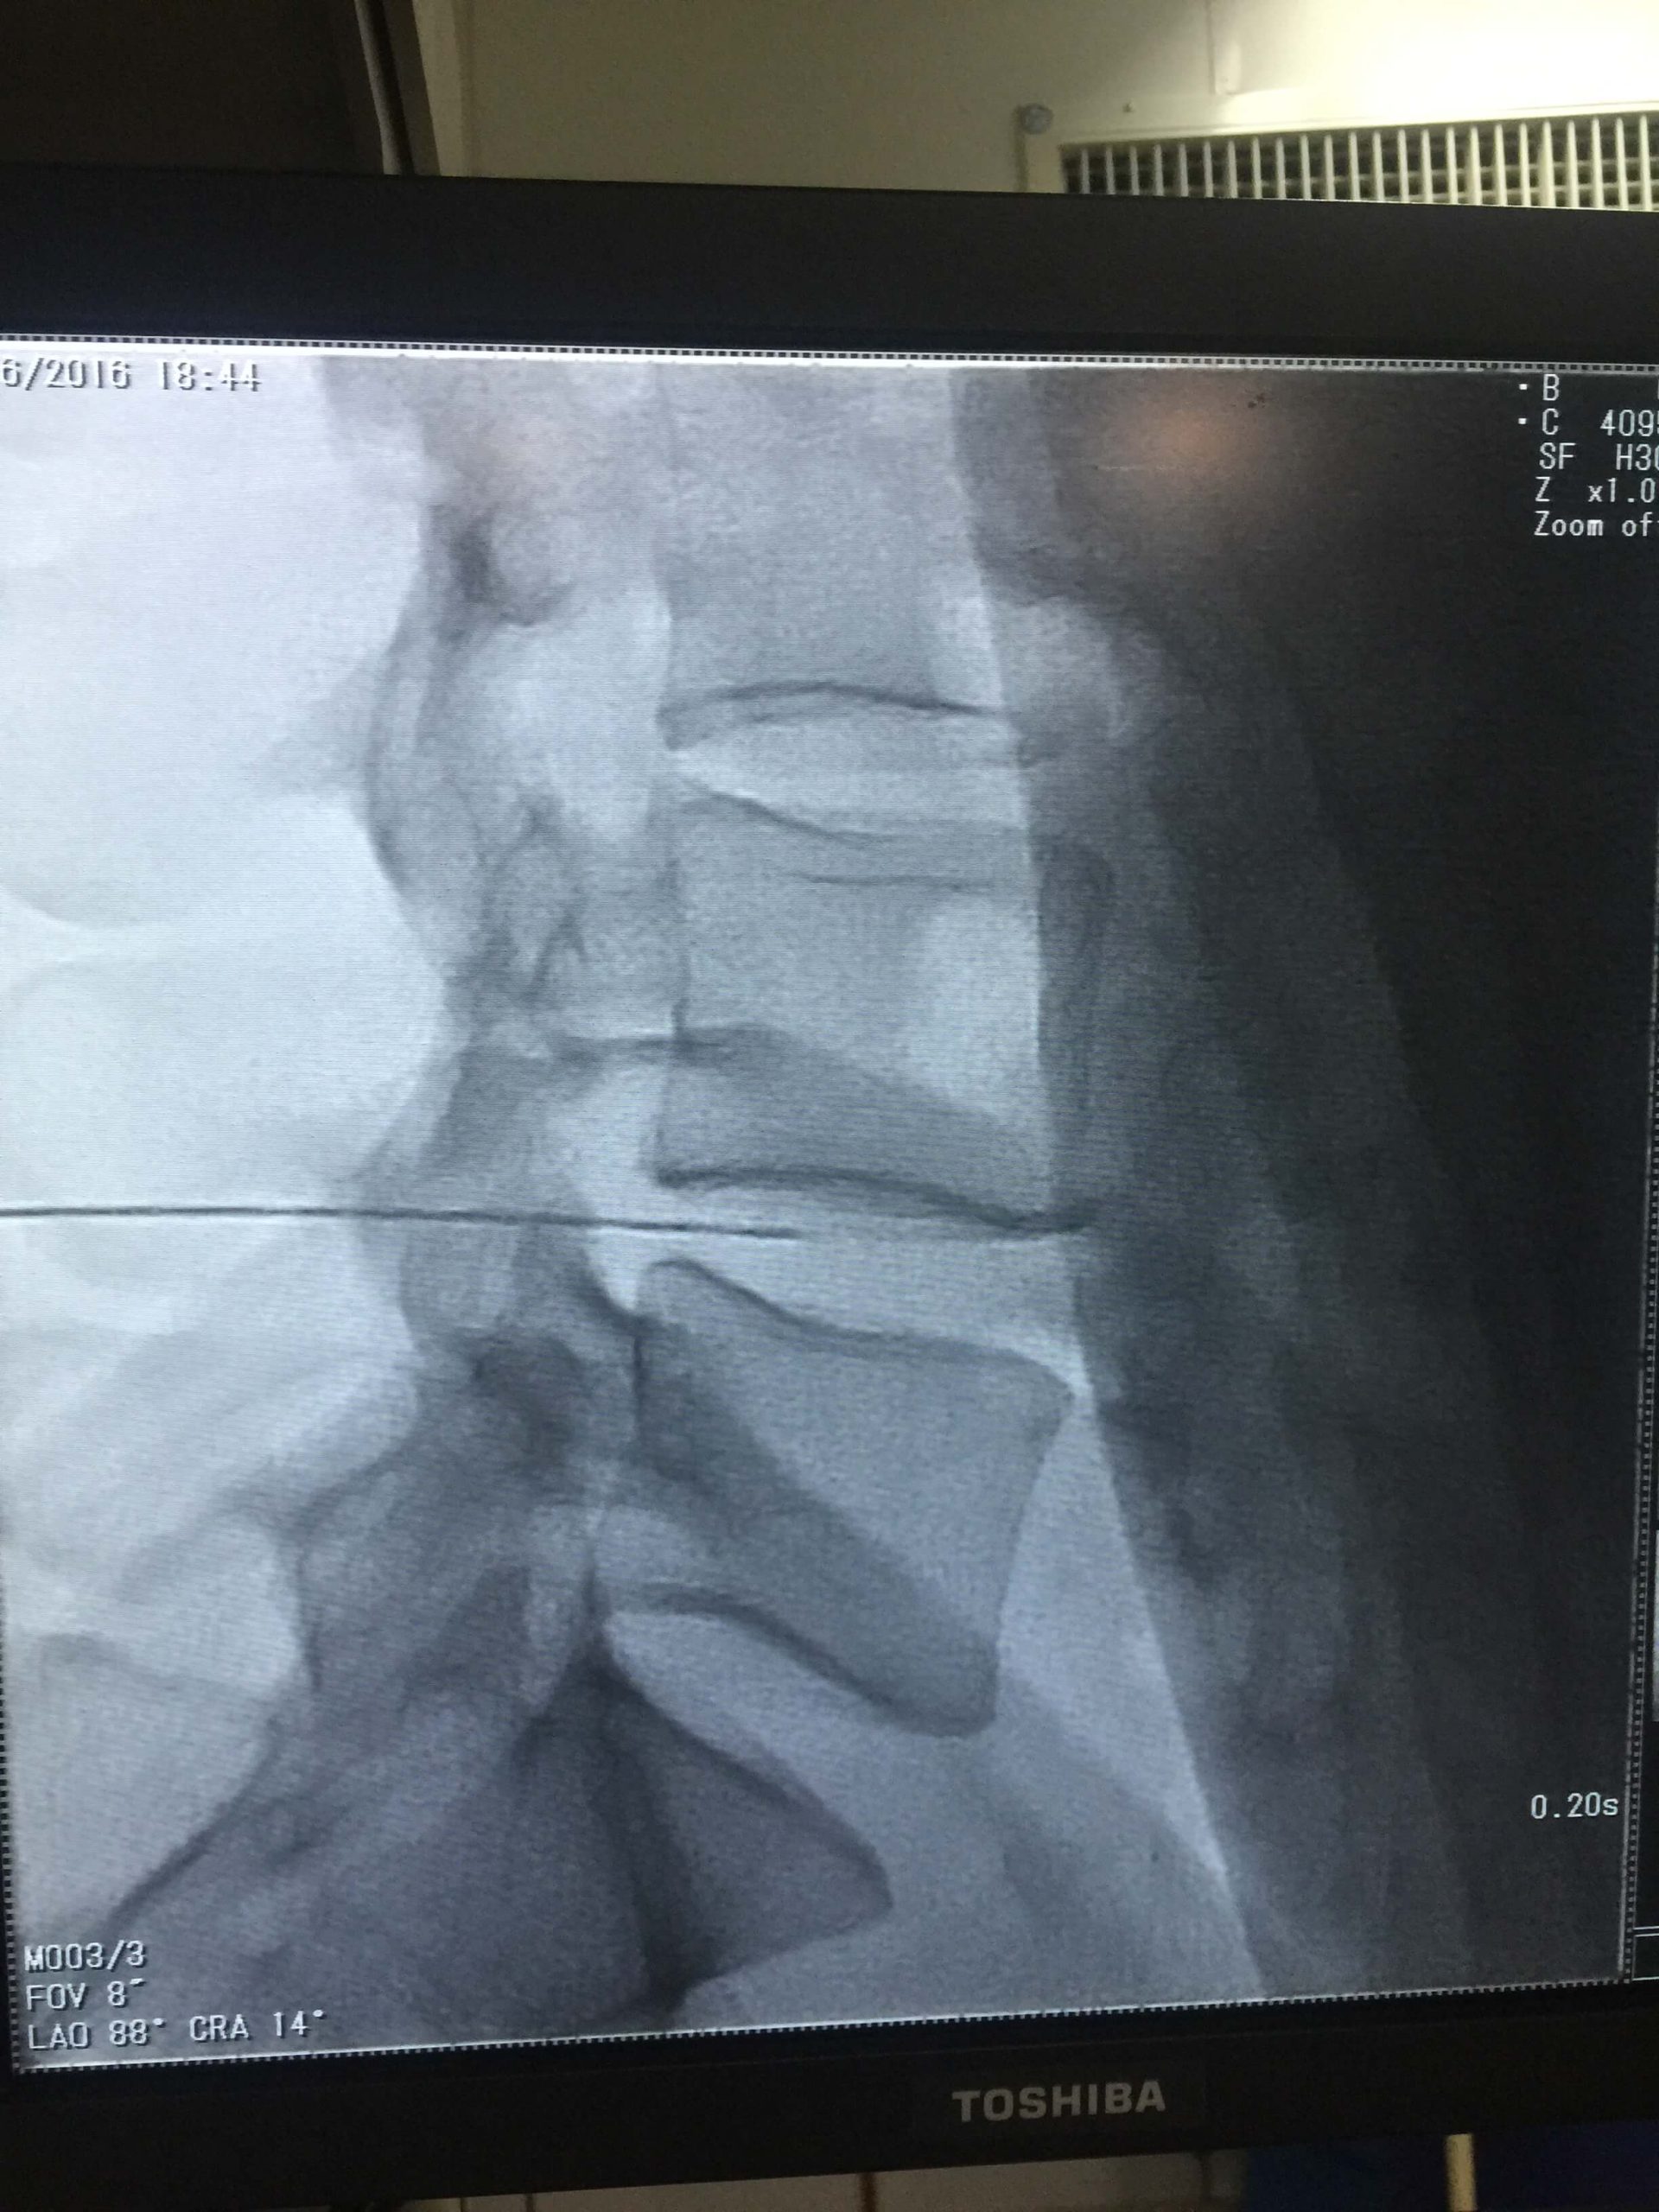

Ozone Therapy (Disc Problems) Overview

Ozone therapy is an innovative treatment that has shown promising results in treating disc problems. This therapy involves injecting ozone gas into the affected area to reduce inflammation and improve blood circulation, thereby promoting the natural healing process. The benefits of ozone therapy are numerous and it is considered an excellent and safest alternative to traditional treatments such as surgery or medication. With its non-invasive approach, it is becoming a popular choice among patients seeking long-lasting relief from disc problems. If you are interested in exploring ozone therapy as a treatment option, please consult with a licensed healthcare professional before proceeding. Their expertise will be key in determining the most effective course of action for your unique case.

Health Tips & Info